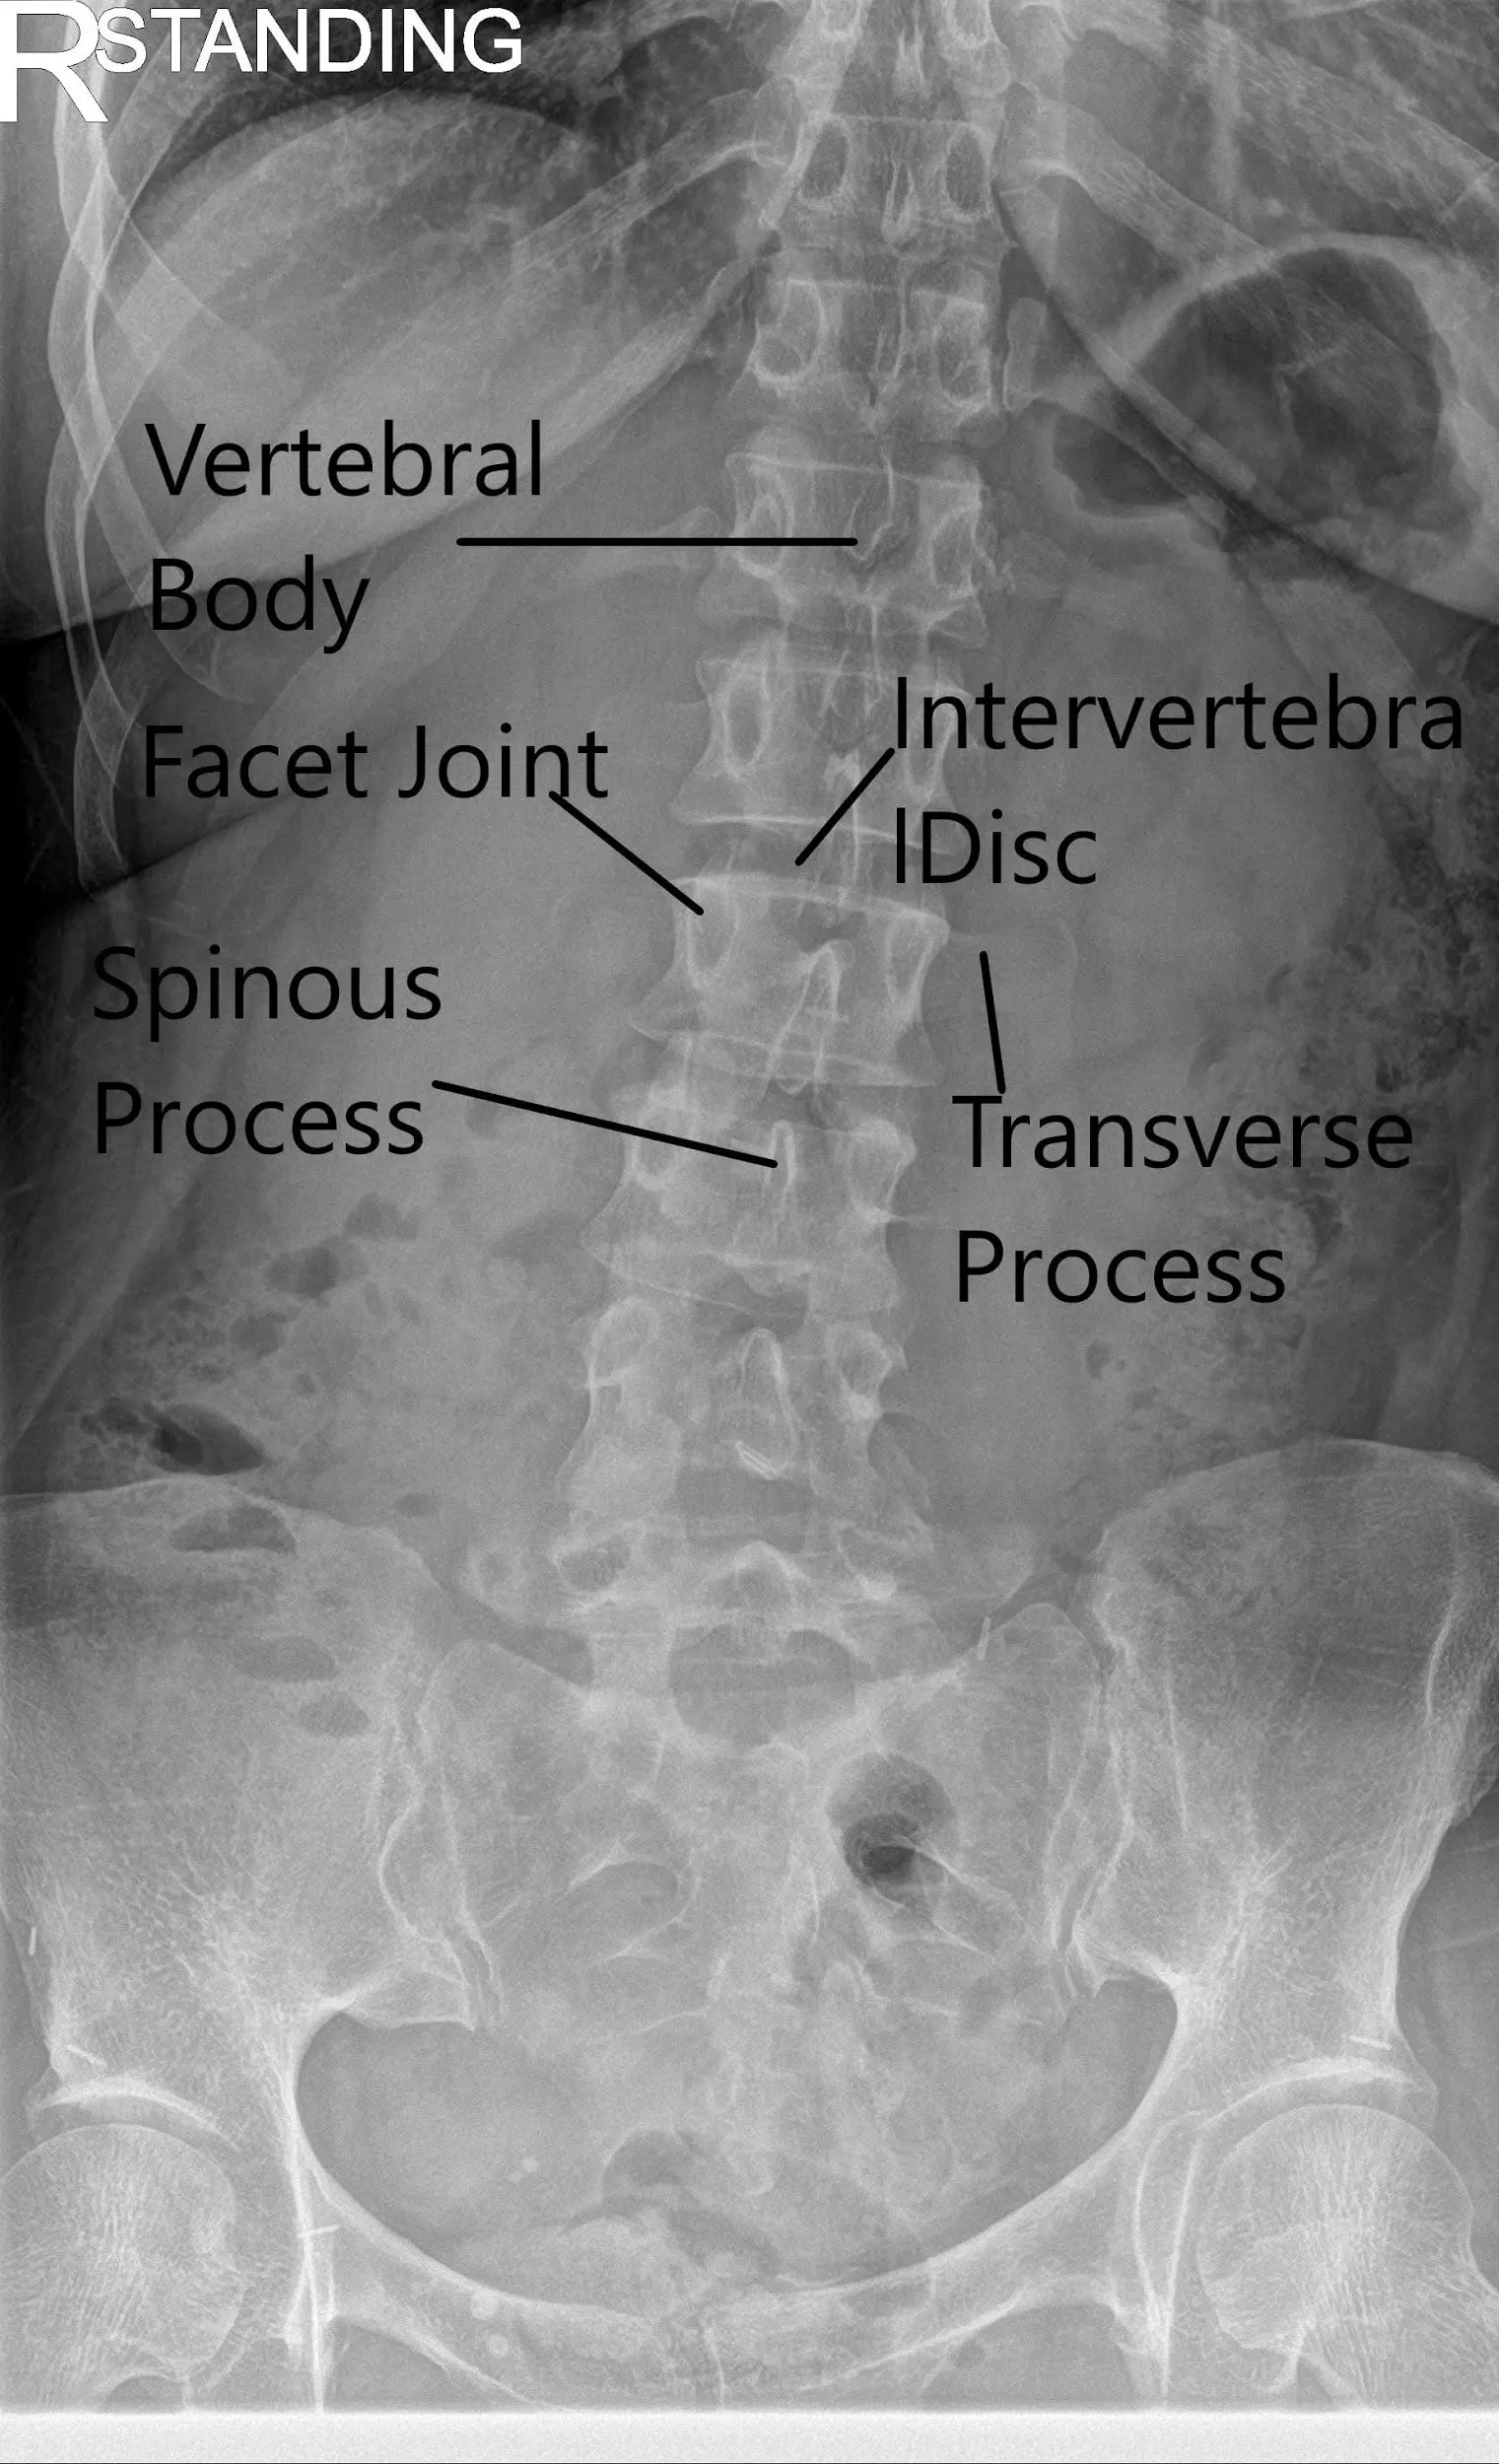

X-ray of the LS spine in AP and Lateral views showing degenerative changes.